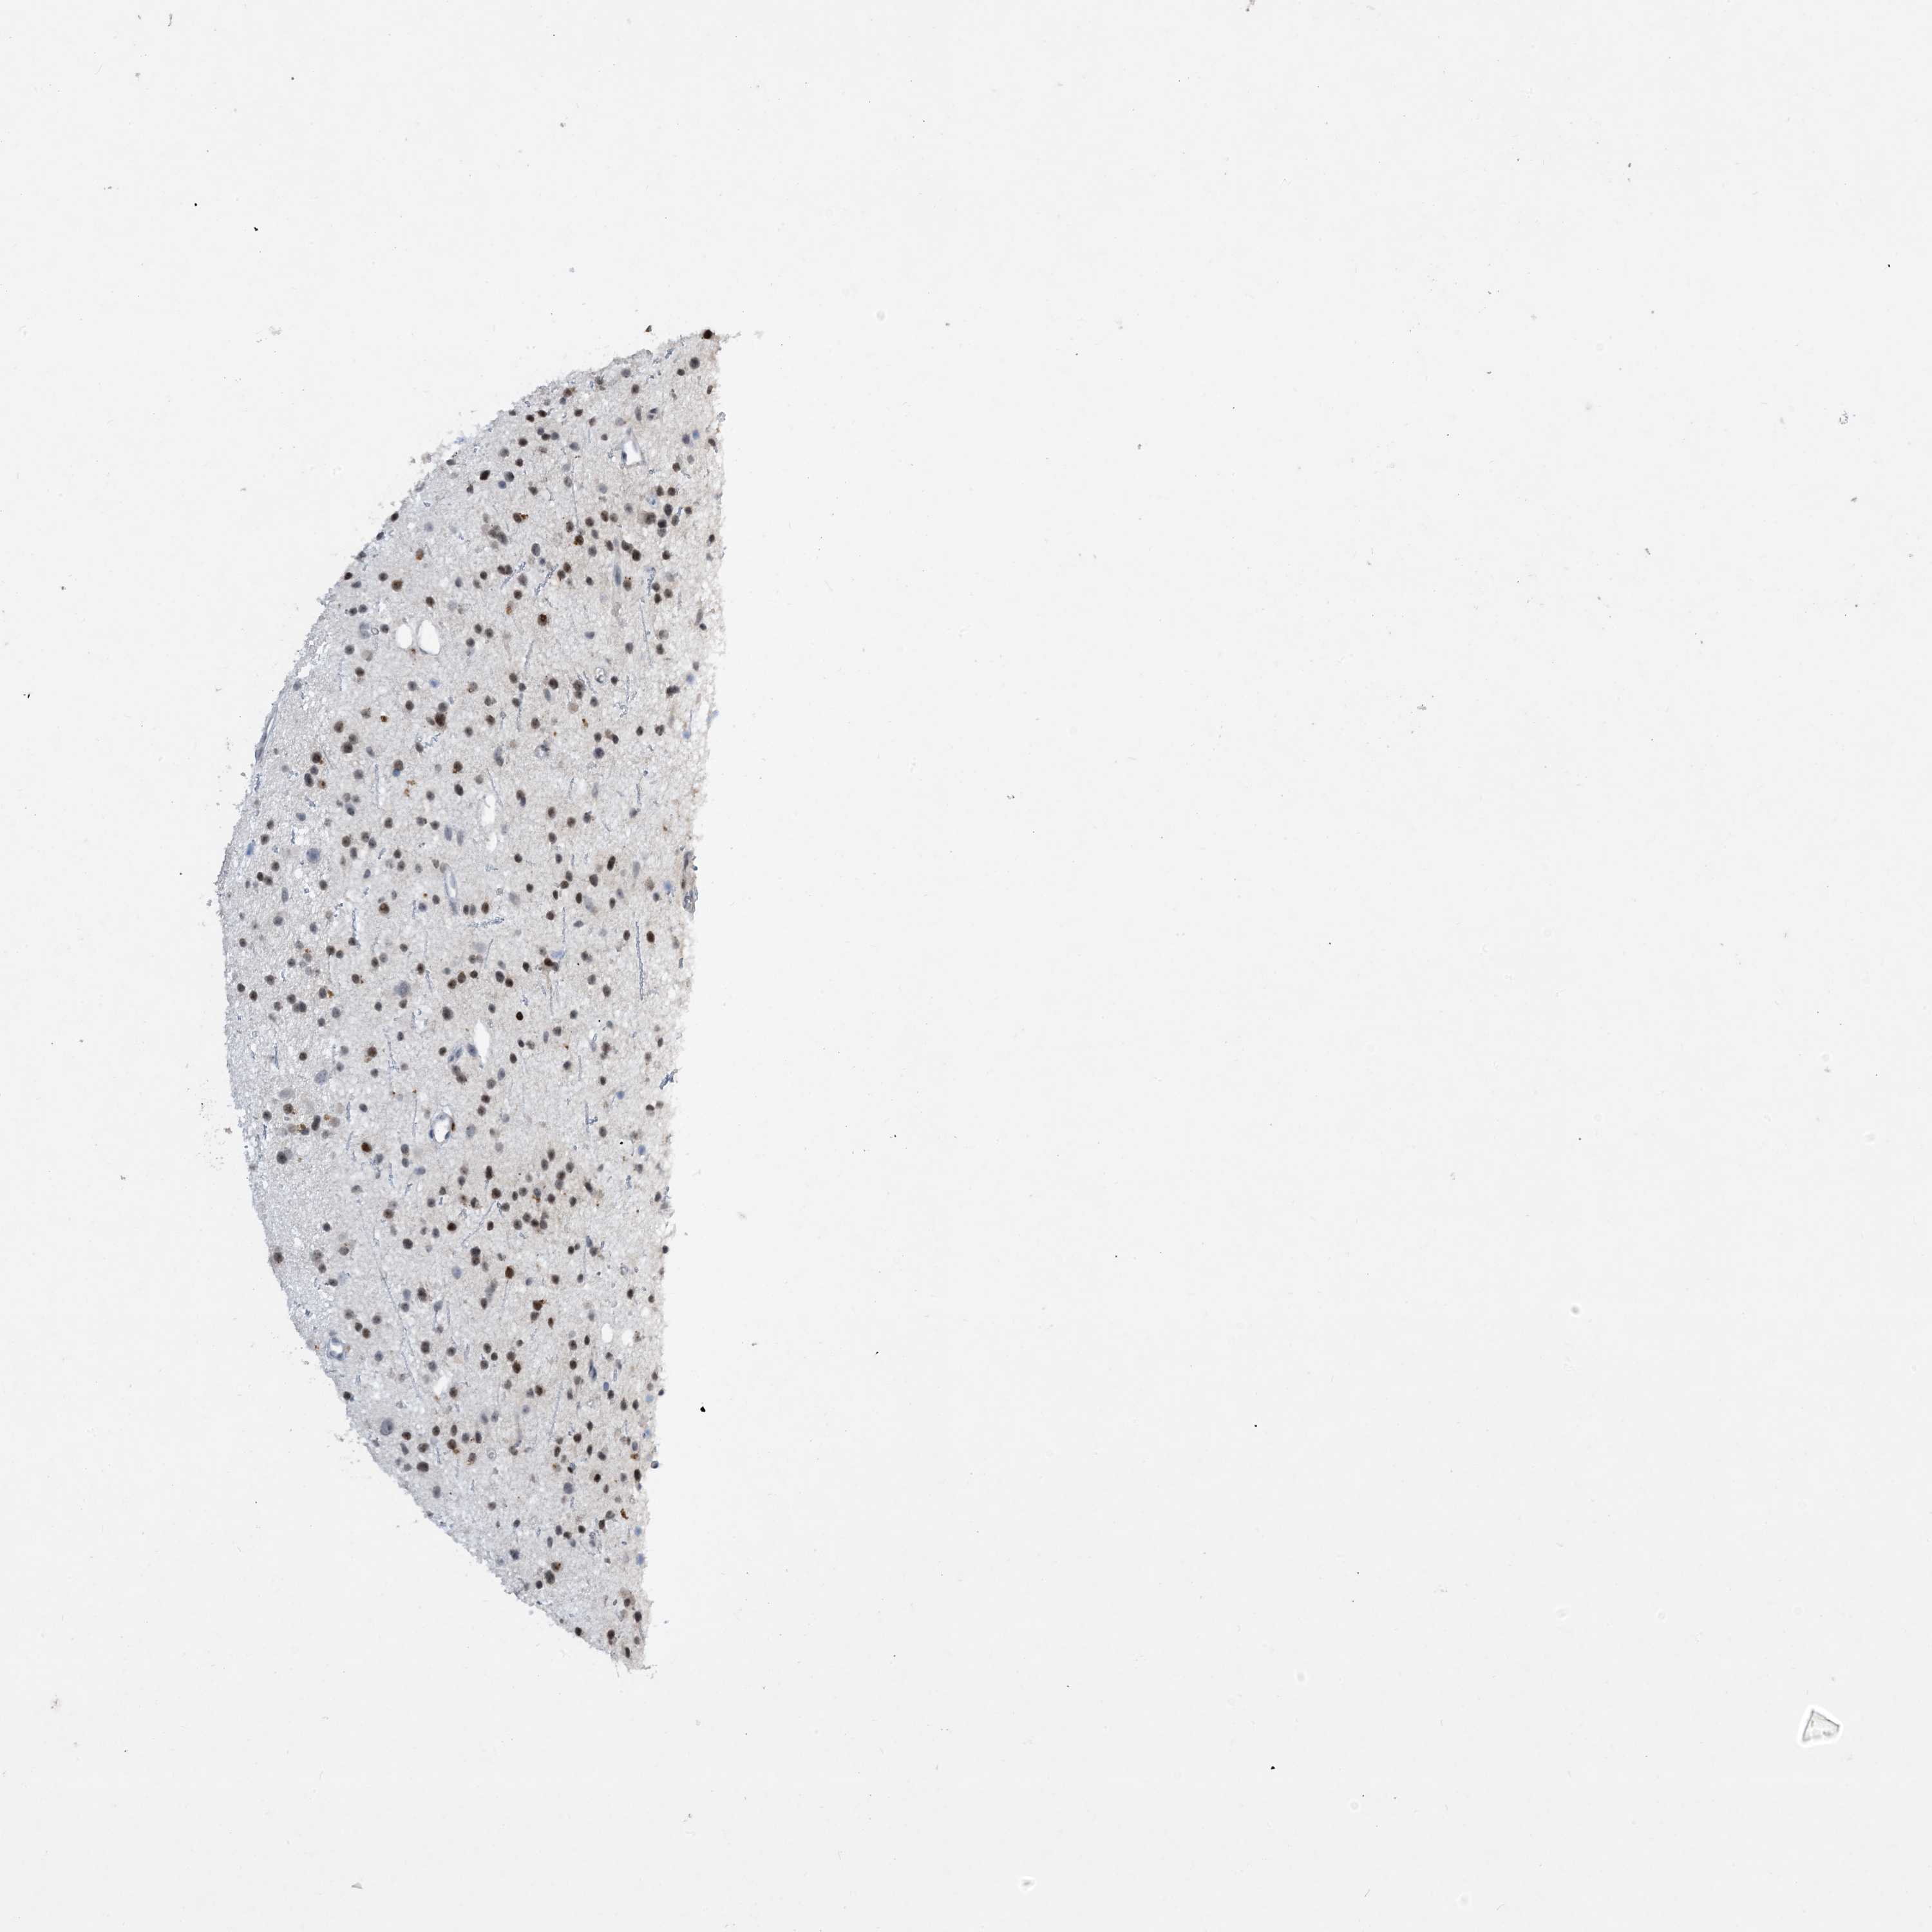

GLIOMA - Protein expressioni

A mouse-over function shows sample information and annotation data. Click on an image to view it in a full screen mode. Samples can be filtered based on level of antibody staining by selecting one or several of the following categories: high, medium, low and not detected. The assay and annotation is described here.

Note that samples used for immunohistochemistry by the Human Protein Atlas do not correspond to samples in the TCGA dataset.

Antibody stainingi

Antibody staining in the annotated cell types in the current human tissue is reported as not detected, low, medium, or high, based on conventional immunohistochemistry profiling in selected tissues. This score is based on the combination of the staining intensity and fraction of stained cells.

Each image is clickable and will lead to virtual microscopy that enables deeper exploration of all samples and also displays staining intensity scores, fraction scores and subcellular localization as well as patient and tissue information for each sample.

Antibody HPA034959

Staining

High

Medium

Low

Not detected

Intensity

Strong

Moderate

Weak

Negative

Quantity

>75%

75%-25%

<25%

None

Location

Nuclear

Cytoplasmic/membranous

Cytoplasmic/membranous,nuclear

Glioma, malignant, High grade

Glioma, malignant, Low grade

Glioblastoma, NOS